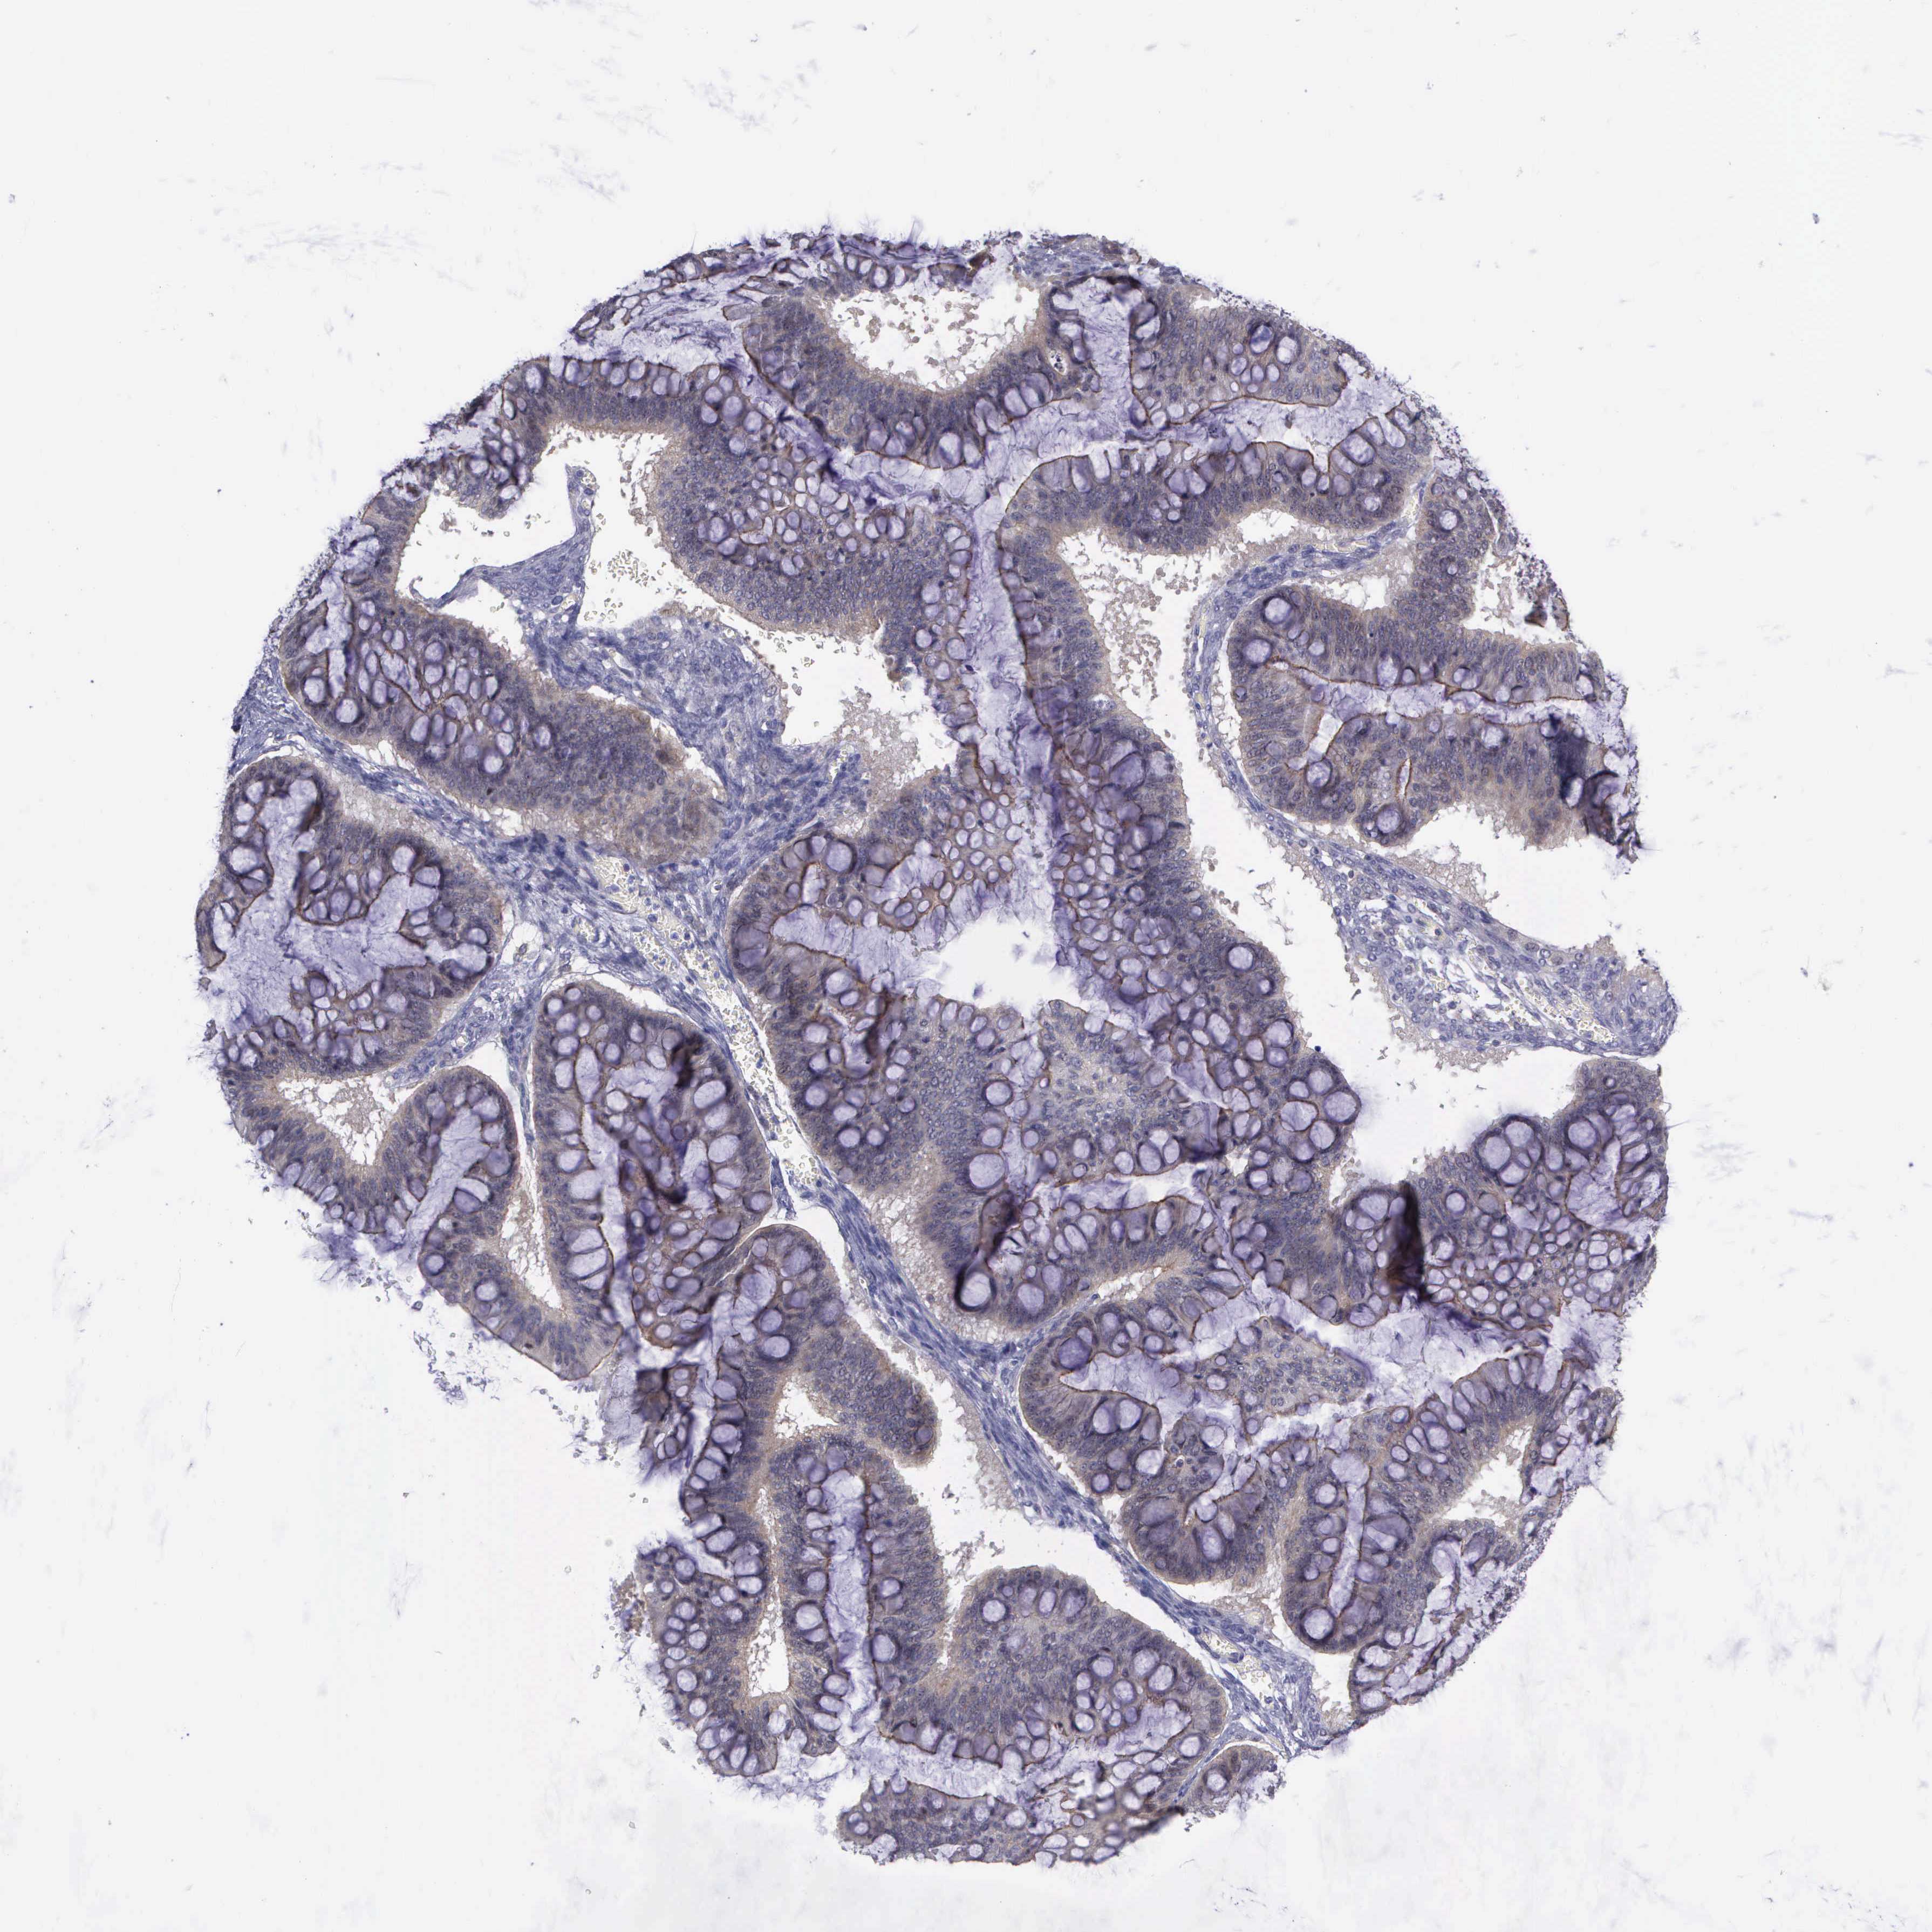

OVARIAN CANCER - Protein expressioni

A mouse-over function shows sample information and annotation data. Click on an image to view it in a full screen mode. Samples can be filtered based on level of antibody staining by selecting one or several of the following categories: high, medium, low and not detected. The assay and annotation is described here.

Note that samples used for immunohistochemistry by the Human Protein Atlas do not correspond to samples in the TCGA dataset.

Antibody stainingi

Antibody staining in the annotated cell types in the current human tissue is reported as not detected, low, medium, or high, based on conventional immunohistochemistry profiling in selected tissues. This score is based on the combination of the staining intensity and fraction of stained cells.

Each image is clickable and will lead to virtual microscopy that enables deeper exploration of all samples and also displays staining intensity scores, fraction scores and subcellular localization as well as patient and tissue information for each sample.

Antibody HPA000639

Staining

High

Medium

Low

Not detected

Intensity

Strong

Moderate

Weak

Negative

Quantity

>75%

75%-25%

<25%

None

Location

Nuclear

Cytoplasmic/membranous

Cytoplasmic/membranous,nuclear

Cystadenocarcinoma, mucinous, NOS

Carcinoma, endometroid

Cystadenocarcinoma, serous, NOS